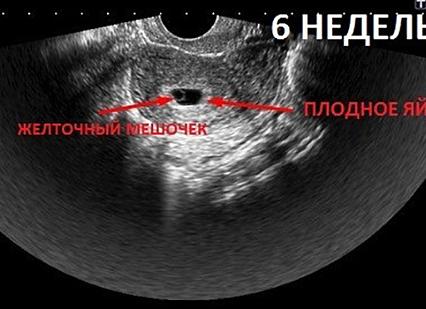

Первое сердцебиение плода на УЗИ

Только женские сердца невозможно обмануть: мамочки инстинктивно чувствуют, что вновь приобретенный тест покажет долгожданные две полоски. Если задержка составляет больше недели, то настало время прояснить ситуацию и определить наличие развивающегося ребеночка в животе у мамочки.